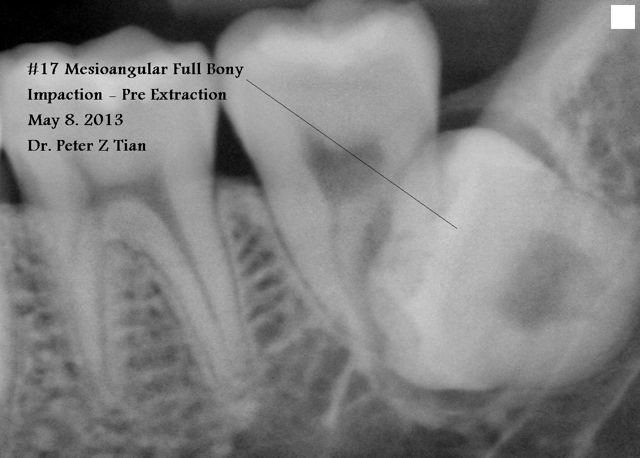

全景片分析表明(图一):下颌第三磨牙近中阻生,似乎非拔不可,而上颌智齿位置太高,拔除非常困难,告诉病人妈妈,她好像讽刺地说口外医生常规拔除四个智齿,为什么你不行?心平气和地解释专家有时也下不了手术台,拔除上颌智齿可能弊大于利,今天先拔除下颌智齿,如果时间充裕,再决定是否拔除上颌智齿,妈妈同意。

1)是否要拔智齿

答:要拔,尤其是左右下颌的二个#17 , #32,有可能造成牙体,牙髄,牙周及牙槽骨病变。见附图,我的一病例#17阻生,造成前面#18远中根严重吸收。